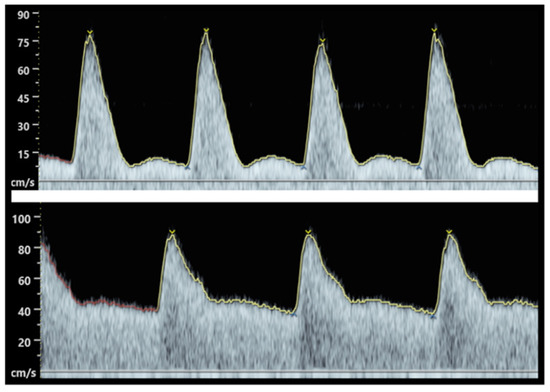

- Nicolaides, K.; Rizzo, G.; Hecher, K.; Ximenes, R. Doppler in Obstetrics; Fetal Medicine Foundation: London, UK, 2002. [Google Scholar]